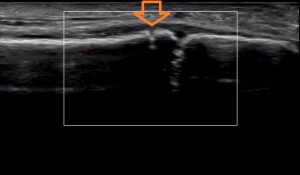

下はエコー画像ですが、矢印の先にある凹んだところが折れているところです。

その右隣にある凹んだところは骨端線です。

エコーで見ると、今回は、骨端線損傷と骨端線の上に亀裂骨折が見られました。

※矢印の先が折れているところ。上下の画像を見比べてみるとわかり易いですね。

矢印の先が折れているところです。

これが痛い原因ですね。おまけに、踵腓靭帯も腫れてます。